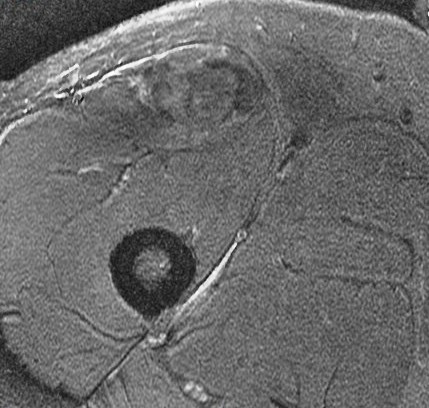

25 y/o work injury, soccer injury.

Maybe his soccer playing is his work? Who am I to ask questions. The indirect head goes on to form the central tendon. There is complete failure of the proximal myotendinous junction and there is an interposed acute hematoma. The hematoma is almost isointense to muscle. Reference article.

rectus femoris indirect head proximal myotendinous junction tear with hematoma( RID2698 )